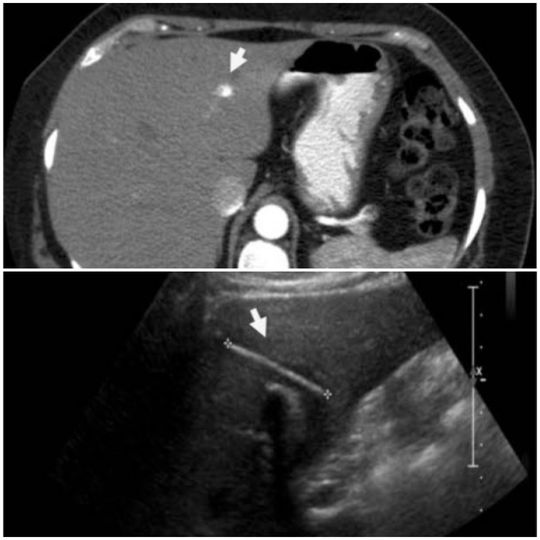

A 45-year-old woman was admitted to the emergency department for recurrent episodes of epigastric pain associated with fever (38.9°C), nausea, vomiting and hypotension. She was on parenteral broad-spectrum antibiotic for suspected intra-abdominal infection. A contrast CT of abdomen confirmed the presence of an elongated structure across the left lateral hepatic segments with abscess in the cavity. The patient was scheduled for an elective exploratory laparoscopy and possible extraction of the foreign body. At the time of surgery, she was found to have inflammation and adhesions between the omentum and the gallbladder. A laparoscopic cholecystectomy was performed. After the 6 months from her surgery, the patient continues to feel well and she denies the recurrence of any of her pre-operative symptoms.